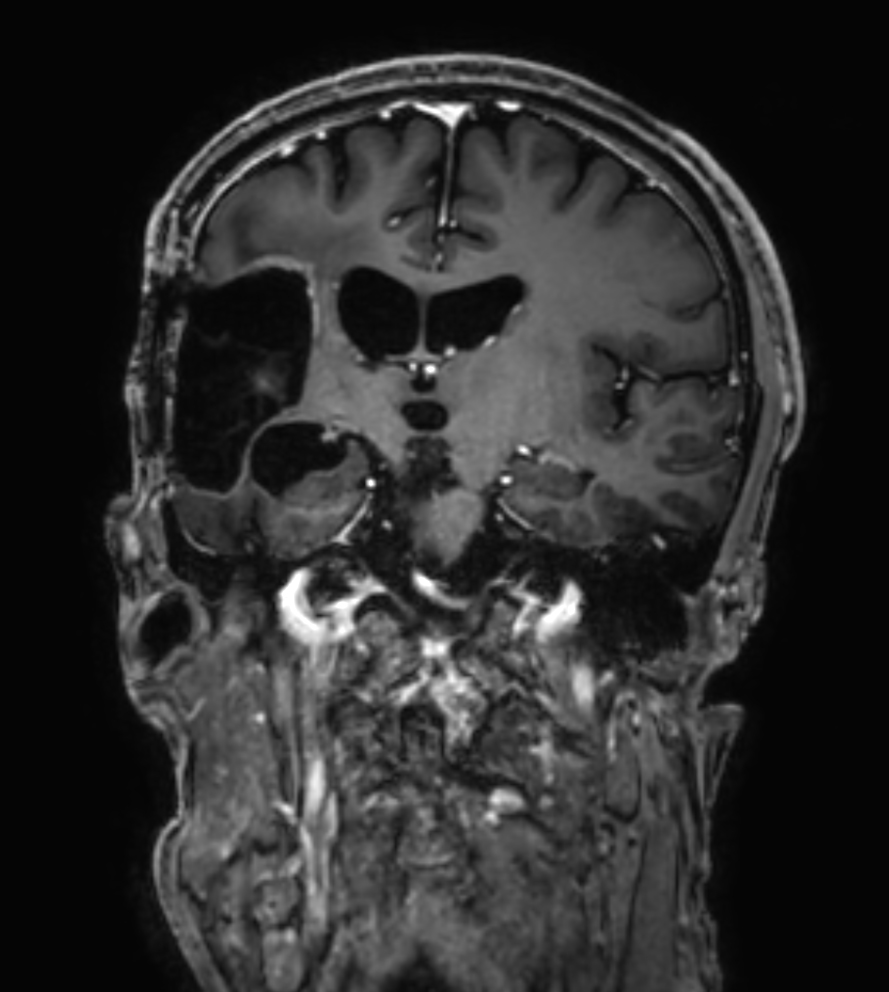

3D T1w TFE - Coronal reformat

3D T1w TFE - Coronal reformat (with gado)

3D T1w TFE - Coronal reformat (high res, with gado)